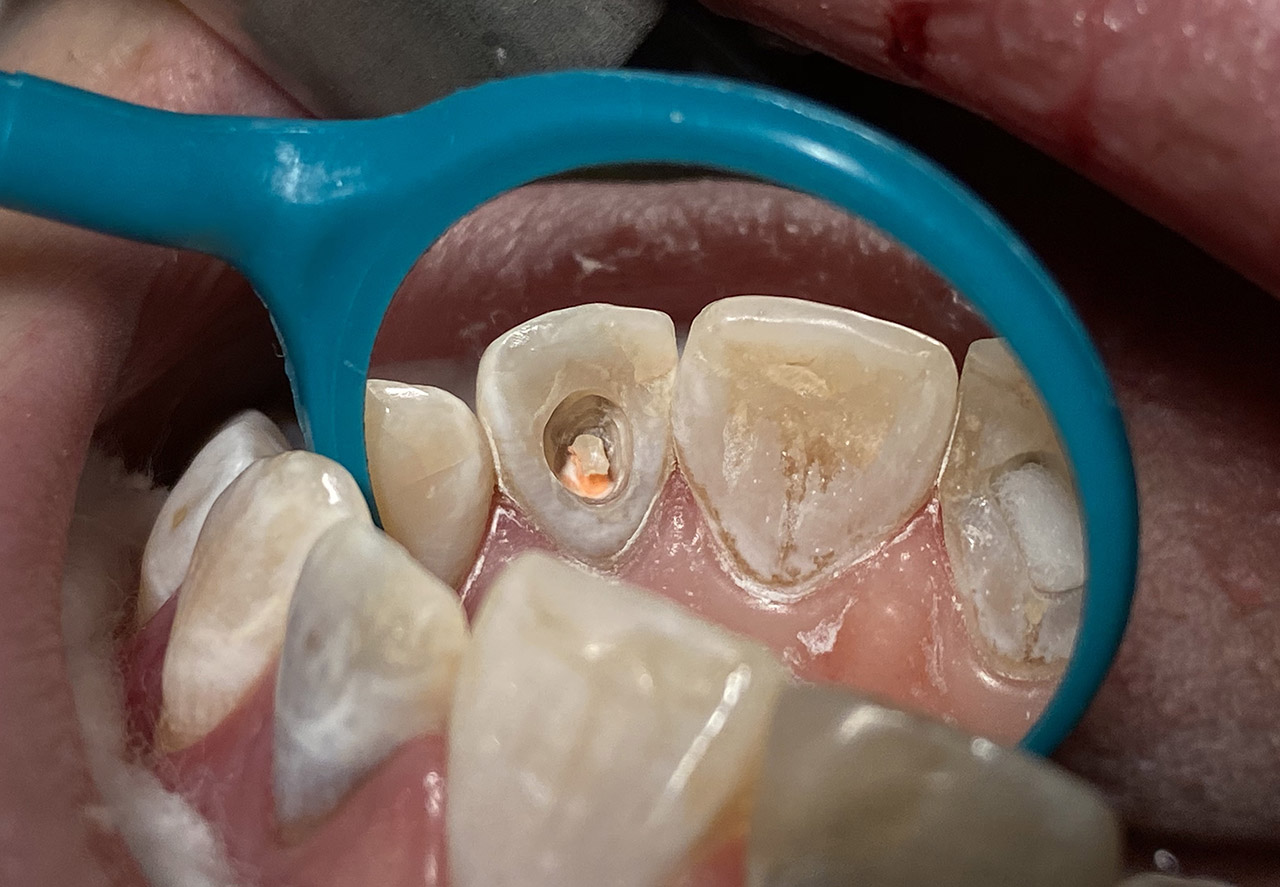

Internes und Externes Bleaching (Bleichen):

Nach Unfall mit E-Scooter unbefriedigendes Ergebnis der Erstversorgung (alio loco). Therapievorschlag: Stiftzähne?

Unsere minimalinvasive Therapie: Revision der Wurzelbehandlungen, danach internes und externes Bleaching, adhäsive Kunststoffüllungen in Schichttechnik. (Titel meiner Diplomarbeit 2003 “Die Vermeidung von Extraktion und Wurzelspitzenresektion durch zeitgemässe Endodontie in der Privatpraxis”)